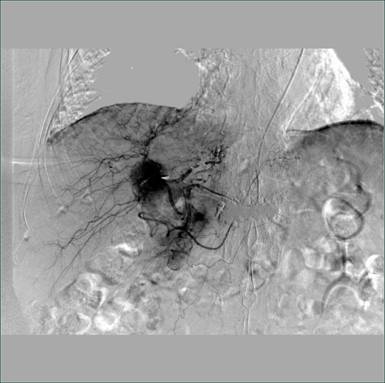

术中造影图片: